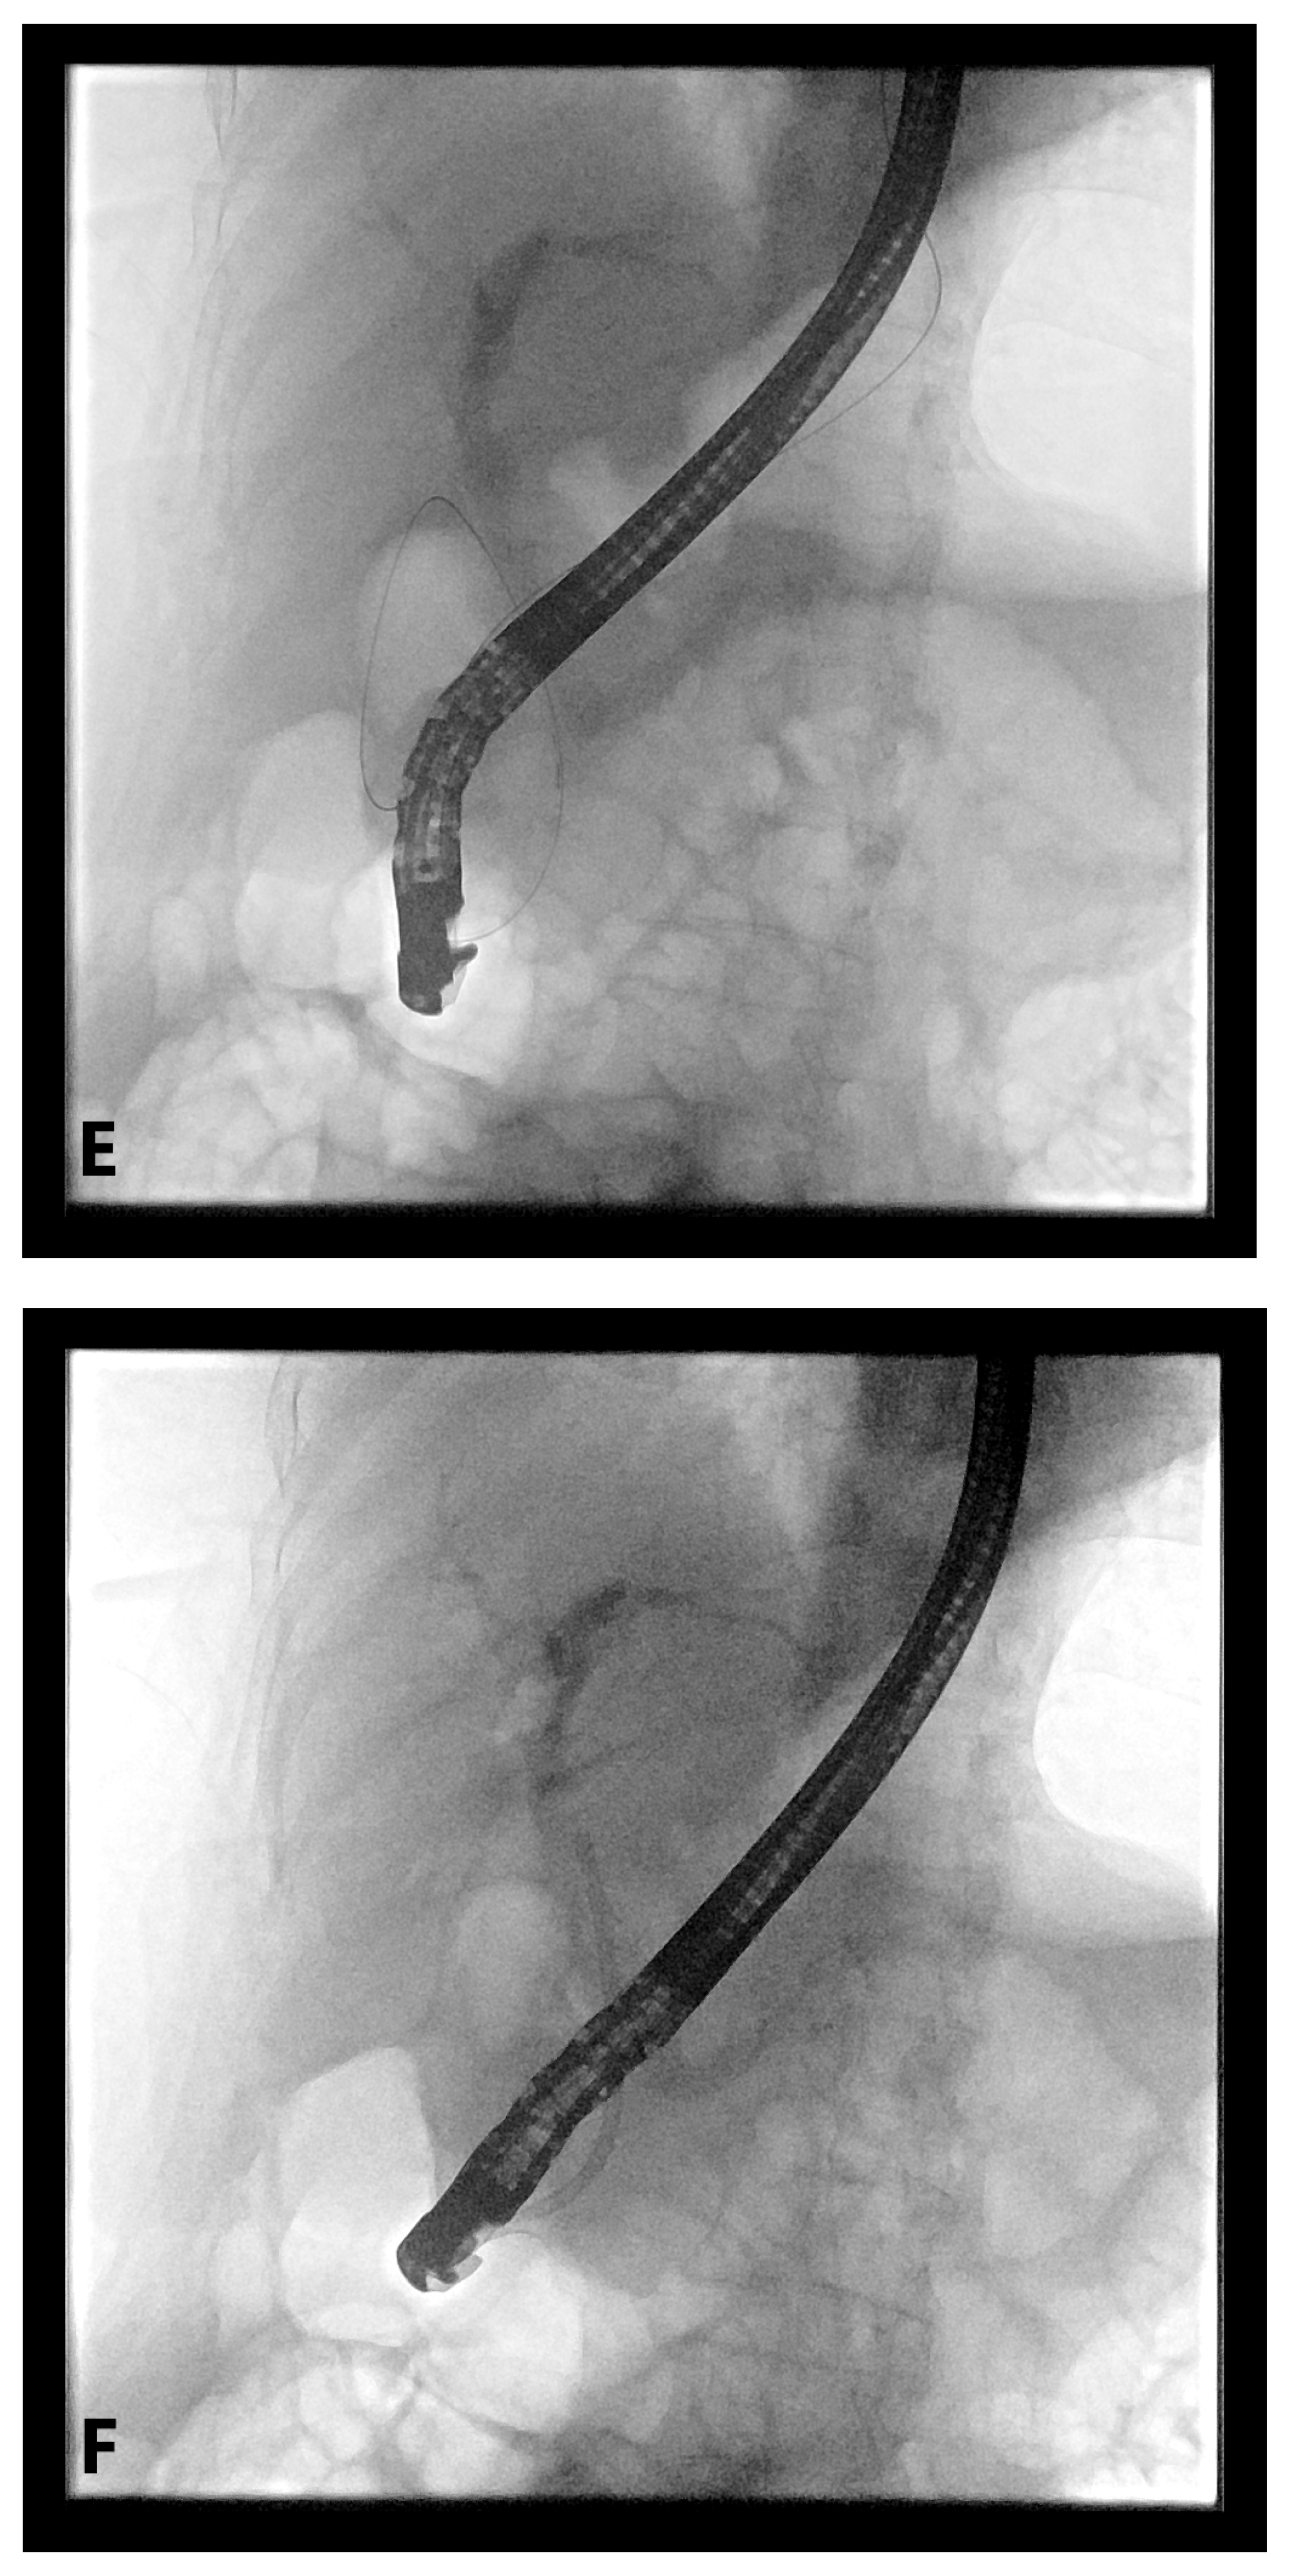

4. EUS-Guided Rendezvous (EUS-RV) Technique

4.1. Advantages

4.2. Disadvantages